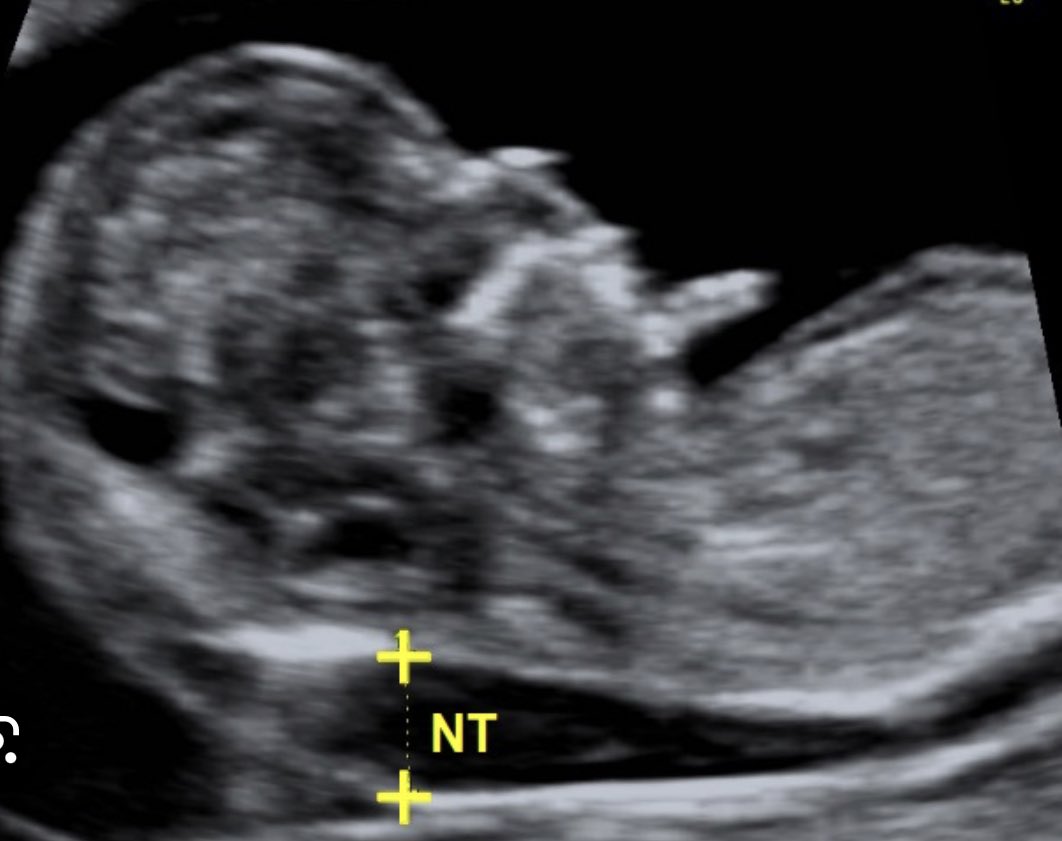

🔹للكشف عن متلازمه داون اثناء الحمل :

🔺تحليل دم الام NIPT

من ١٠ اسابيع وفوق والدقه ٩٩،٩٪

❌ لايمكن ابداً تشخيص متلازمه داون او اي مشكله في كروموسومات الجنين بالاشعه العاديه ولا الثلاثيه او الرباعيه